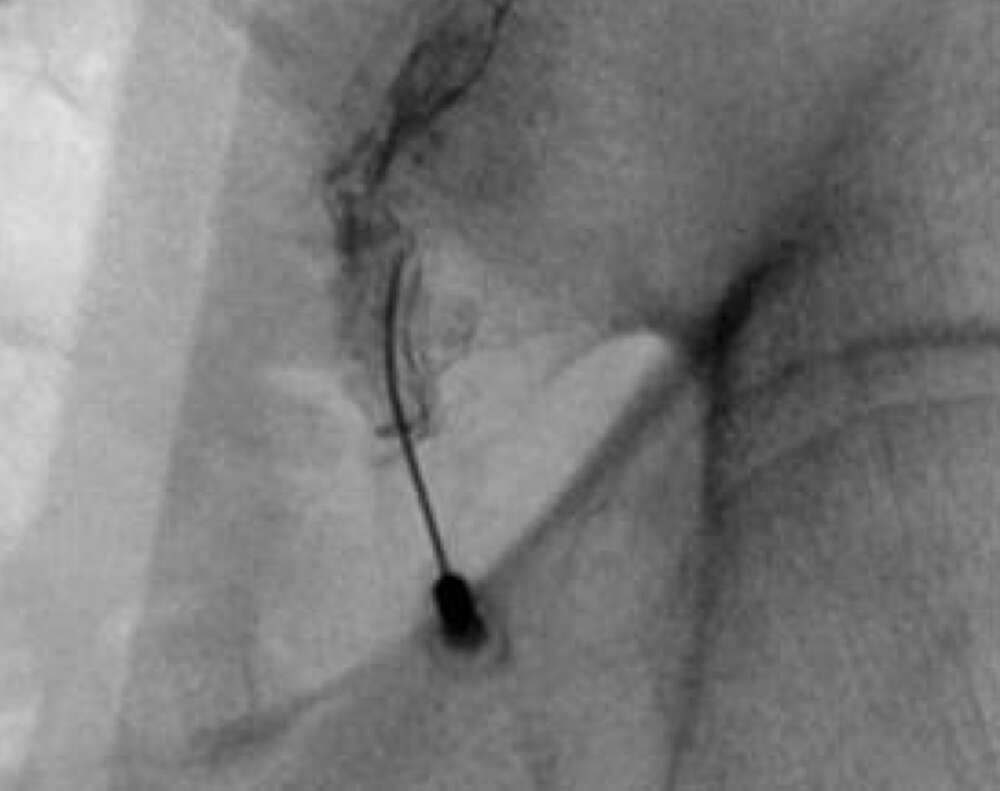

- Bi-lateral SI joint degeneration with pain post revision surgery verified via SI joint block injection.

- Bilateral SI joint fusion using the iFuse 3D™ Implant System, August 2020